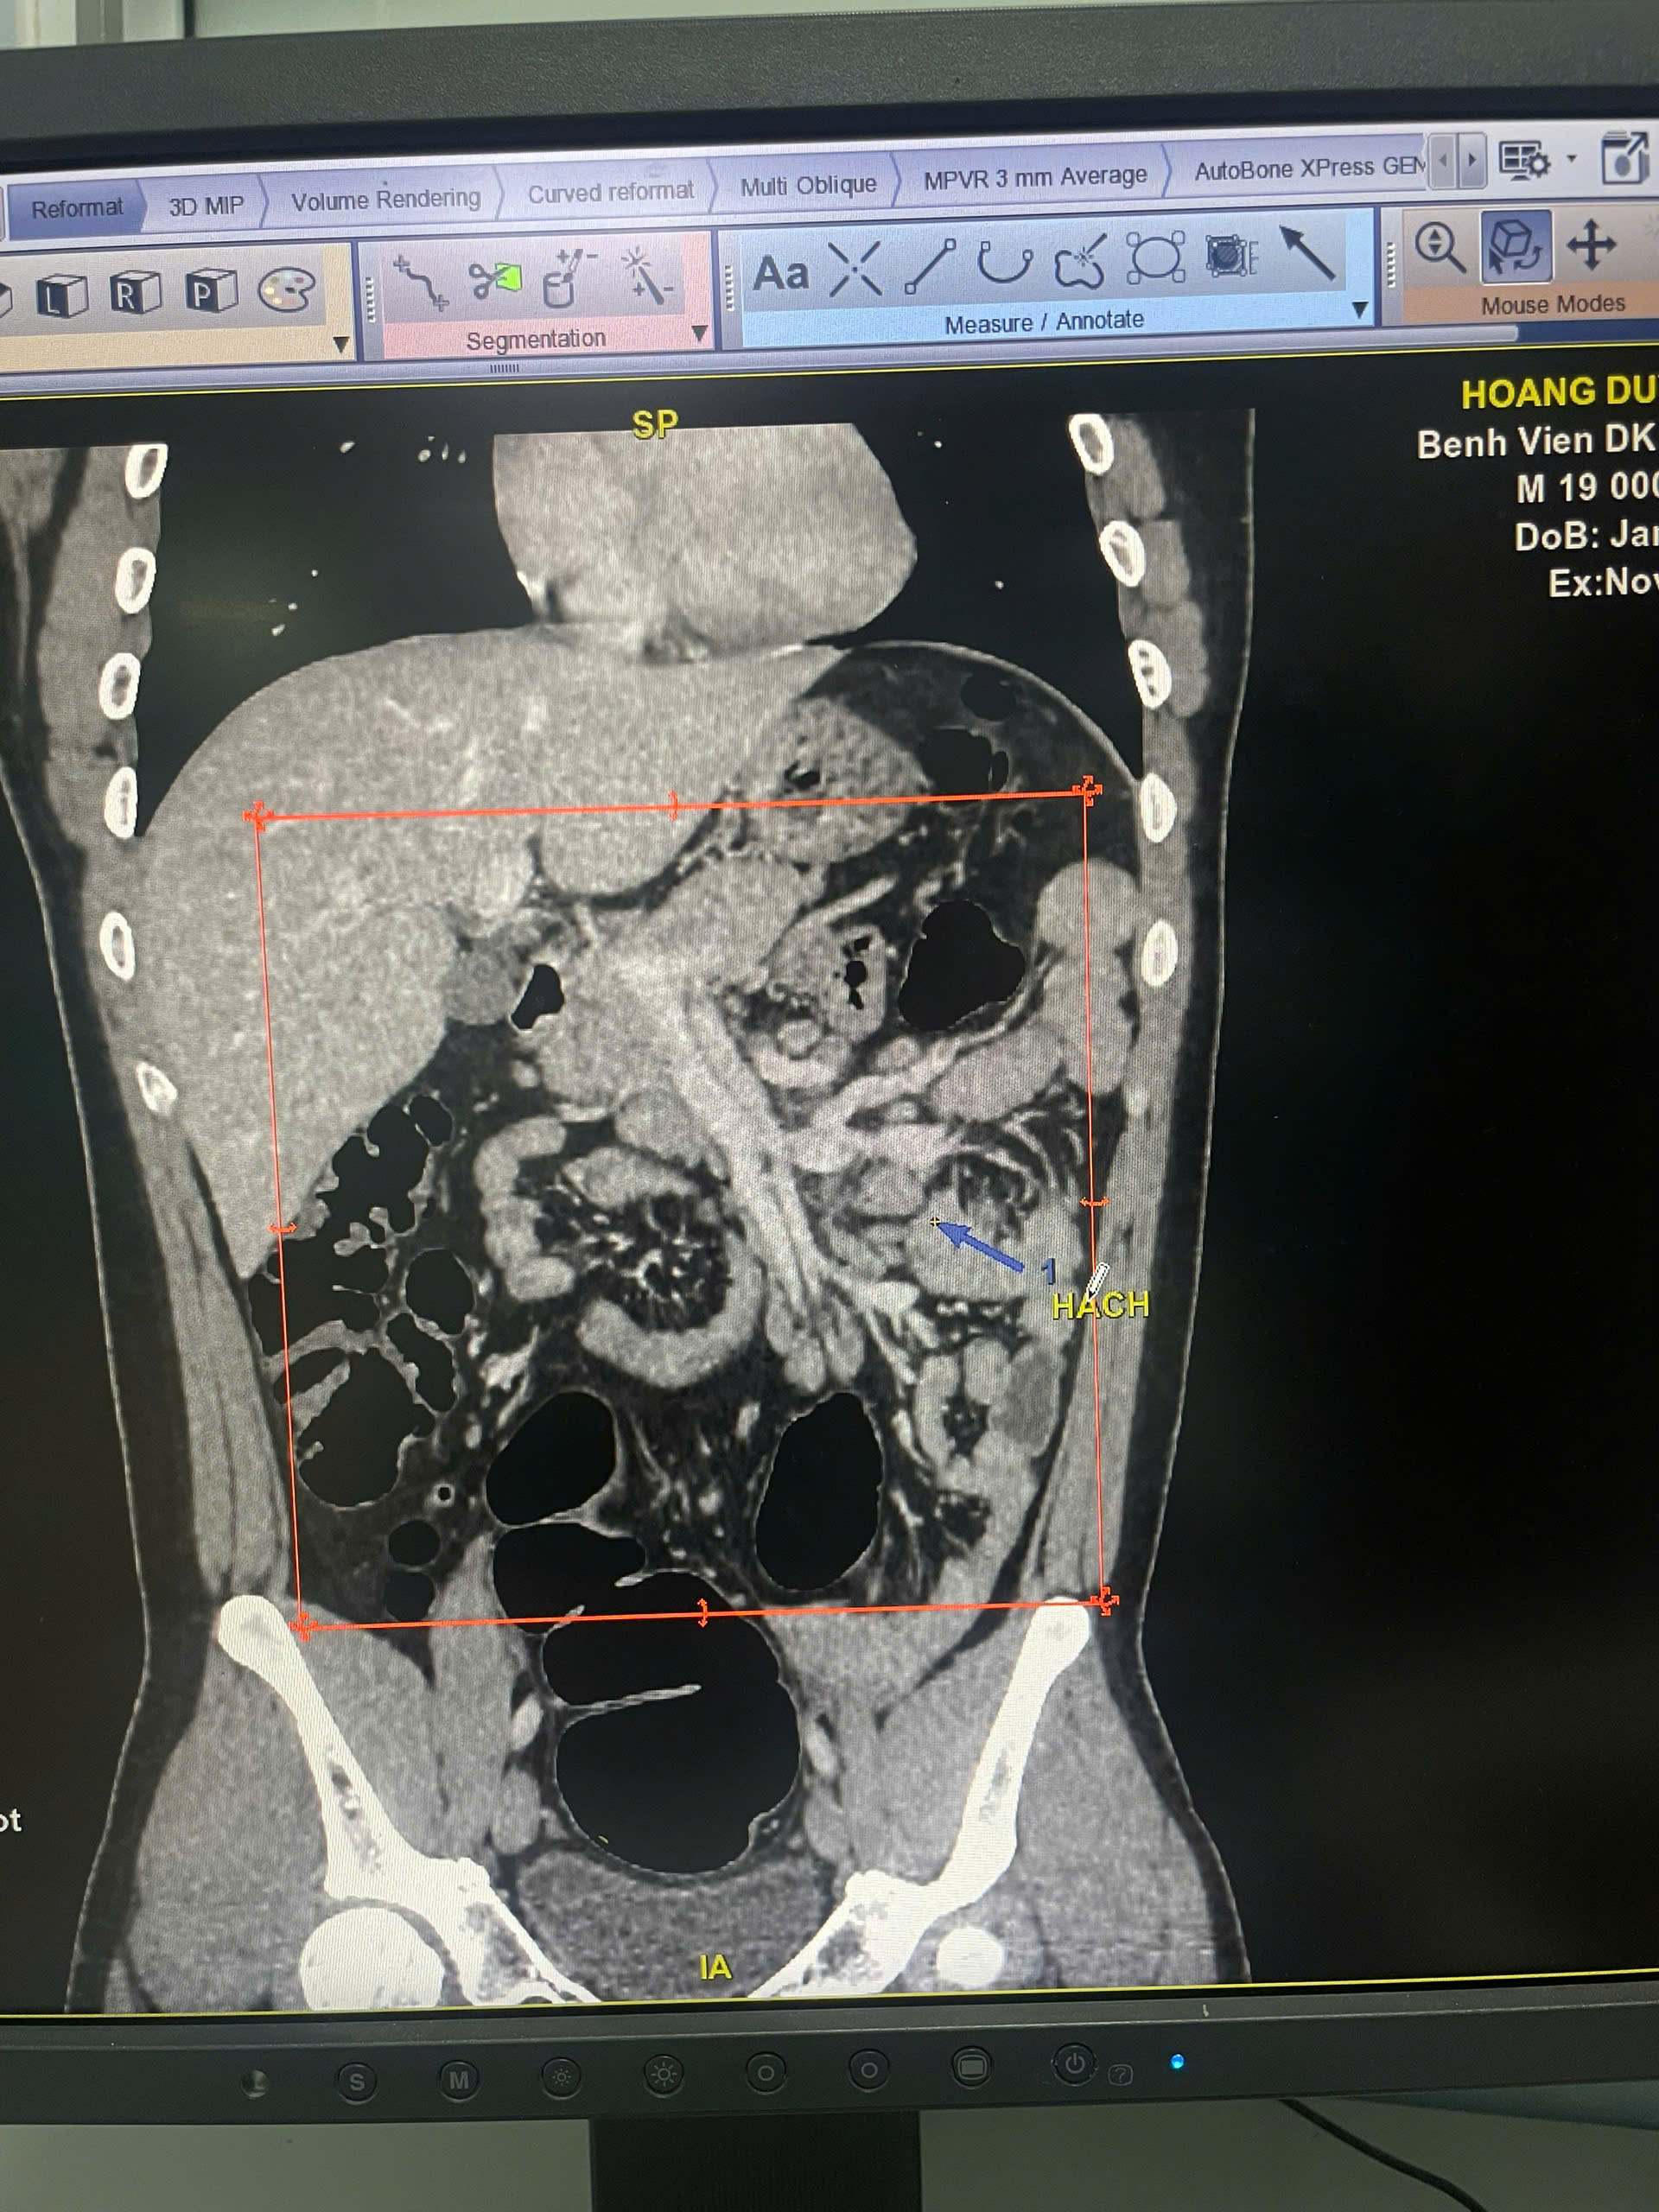

Bác sĩ đã chỉ định chụp CT-Scanner ổ bụng có tiêm thuốc, nhằm loại trừ các tổn thương tiềm ẩn. Kết quả cho thấy:

+ Khối đặc vùng thượng thận phải kích thước 58 × 52 × 44 mm

+ Nhiều hạch ổ bụng chưa loại trừ lymphoma

Hình ảnh kết quả CT- Scaner của người bệnh

Nhờ chất lượng hình ảnh sắc nét của hệ thống CT hiện đại cùng quy trình đánh giá nhanh chóng tại BVĐK Hà Đông, bác sĩ đã kịp thời đưa ra hướng xử trí chuyên môn, giúp bệnh nhân tránh được nguy cơ chậm trễ trong chẩn đoán.